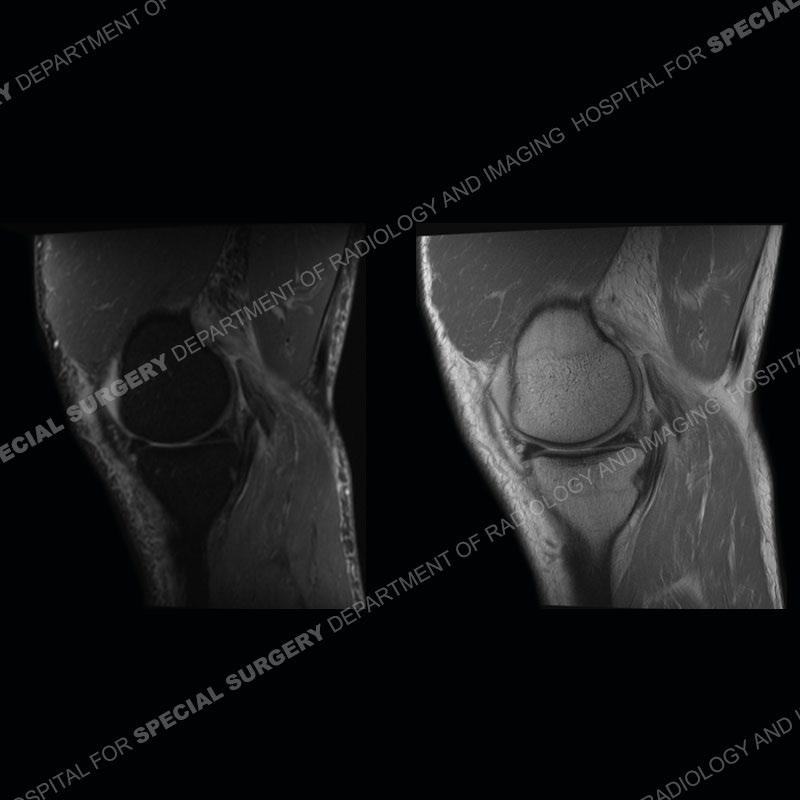

The radiographs show degenerative change of the medial compartment and a varus knee, but they are not germane to this case. No acute bony injury is present. The MRI shows edema of the posterior medial knee/soft tissue and a focal area of a partially disrupted low signal structure. The details are kept at a minimum in the findings of this case on purpose.